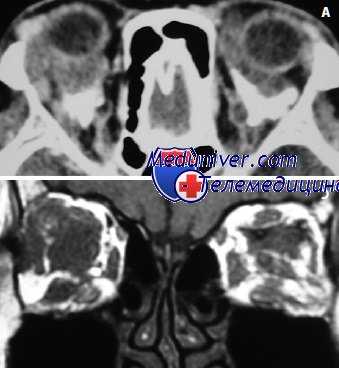

При расположении железистой опухоли ближе к конъюнктивальной поверхности она в начальной стадии развития вызывает только гиперемию конъюнктивы, потом приводит к воспалению последней, а затем уже начинает выпячивать се. По мере роста и последующего увеличения опухоли, она все больше и больше приподнимает и натягивает конъюнктиву и тем: самым больше контактирует с ней, усиливая сперва воспалительный процесс, а затем вызывая и воспалительный отек всей соединительной оболочки века (хемоз). Нередко такой хемоз приводит к возникновению слипчивого конъюнктивита, а последний в свою очередь — к симблефарону, что является характерным для аденогенного рака.

Позже, по мере увеличения и усиления роста опухоли на передней поверхности века начинают выступать безболезненные одиночные или множественные узелковые образования хрящевой плотности, размером от лесного до грецкого ореха или все веко принимает ясно выраженную дольчатость. Начинают появляться первые функциональные расстройства века — ограничение подвижности его, в особенности верхнего.

Если в этот период вывернуть веко, то перед нами предстанет папиллярно разбухшая конъюнктива, сквозь которую заметна просвечивающая бледно-желтая, иногда бугристая опухоль мейбомиевой железы. Сама же конъюнктива не изъязвлена, но может быть покрыта мелкими серыми узелками.

Увеличение роста опухоли приводит к дальнейшему ограничению подвижности века, к появлению птоза. В дальнейшем веко начинает оттесняться от глазного яблока увеличивающейся плотной опухолью. Однако и при таком закрытом веке опухоль все же длительно не прорастает кожу и она продолжает оставаться достаточно подвижной либо (при значительном натяжении) ограниченно подвижной. Потом кожа истончается и атрофируется и уже значительно позже спаивается с опухолью. После спаяния с кожей века опухоль может и прорасти ее, но опять-таки не по всей поверхности сильно увеличенного века, а только в некоторой части его.

В этой стадии опухолевого роста аденогенный рак обычно скорее прорастает конъюнктиву, чем кожу века. Конъюнктива века в каком-либо месте прорывается и через образовавшееся отверстие выступает серовато-красного цвета опухоль вида цветной капусты. На перфорации возникает раковая язва с плотным, неровным, легко кровоточащим дном и индурированными краями. Опухолевая язва начинает распространяться по конъюнктиве, переходит на конъюнктиву склеры, прорастает се, распространяется на слезное мясцо, начинает врастать в глазное яблоко и, наконец, проникает даже в орбиту. Такие случаи всегда оканчиваются летально.